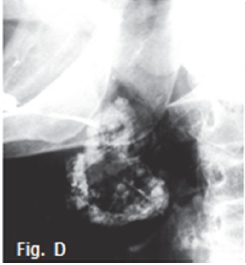

Fig. A is a photograph of a 65 year old male patient presenting with a slow growing swelling of the parotid gland on the right side of the face, which he noticed about eight months ago. Sialography of the parotid gland (Fig. B) shows that contrast medium uptake is prevented by tumour formation, resulting in a poorly imaged right parotid gland (arrow). Fig. C is an axial CT of the same patient demonstrating an ill-defined tumour with an infiltrative margin, indicating malignancy. The right masseter muscle also lacks definition because of infiltration by a malignant tumour (red arrow). A diagnosis of an epidermoid carcinoma was made. The tumour was termed mucoepidermoid by Stewart et al in 1945, who considered it to be divided into benign and malignant types. The WHO regards this tumour as a lesion with malignant potential but believes that, in a variety of clinical instances, it is inappropriate to call any of these tumours "carcinomas". The WHO consider this neoplasm to be intermediate between adenoma and carcinoma. Thirty percent of mucoepidermoid malignancies occur in the salivary glands and appear commonly in the 3rd to 4th decades. The sialogram in Fig. D shows irregular non filling defects suggestive of a malignant pleomorphic adenoma (malignant mixed tumour). The CT sialogram (Fig. E) of the same patient shows an ill-defined tumour mass (arrow). Pathologically, malignant pleomorphic adenoma results from the transformation of the epithelial tissue in a pleomorphic adenoma. These tumours occur predominantly in patients older than 50 years. The transverse T1 weighted MRI scan (Fig. F) of an adenocarcinoma of the right parotid gland shows a poorly defined, non-homogeneouus, infiltrating mass (arrow). Adenocarcinomas most commonly involve the minor salivary glands and submandibular glands, accounting for 5% to 10% of salivary gland tumours. A break in the duct and leakage of contrast medium are sialographic signs of malignancy, and are usually found in epidermoid carcinoma, adenocarcinoma, and high-grade mucoepidermoid carcinoma. However, most of the malignant tumours have a low rate of malignancy.